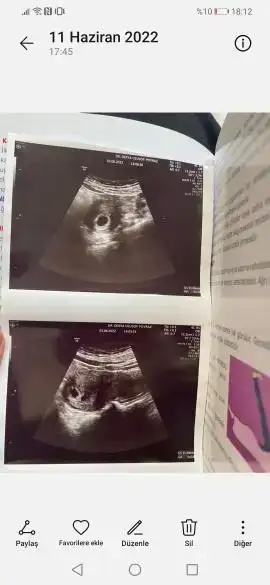

Son karından ultrason görüntümüze göre yorum yapar mısın

Eklentiler

• 7 haftalık.webp

7 haftalık.webp

48,3 KB · Görüntüleme: 57

Benim için de tahmin yapar mısın 6+1 ve 7+4 ultrasonlar

• 597745.webp

597745.webp

11,4 KB · Görüntüleme: 66

• 597744.webp

597744.webp

10,8 KB · Görüntüleme: 65